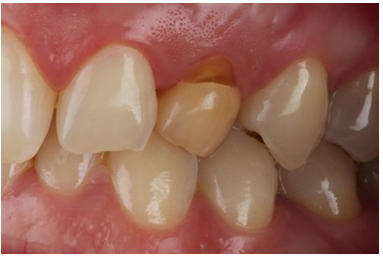

A 40-year-old female patient presented to the private practice of one of the authors with a chief complaint of unaesthetic concern of her deciduous teeth #63 (Figure 1). According to the clinical examination and x ray, tooth #23 was non erupted and was retained on the palatal region Tooth #63 presented as a dark tooth with a non-carious cervical lesion at the vestibular aspect and an obvious smaller size (Figure 2).